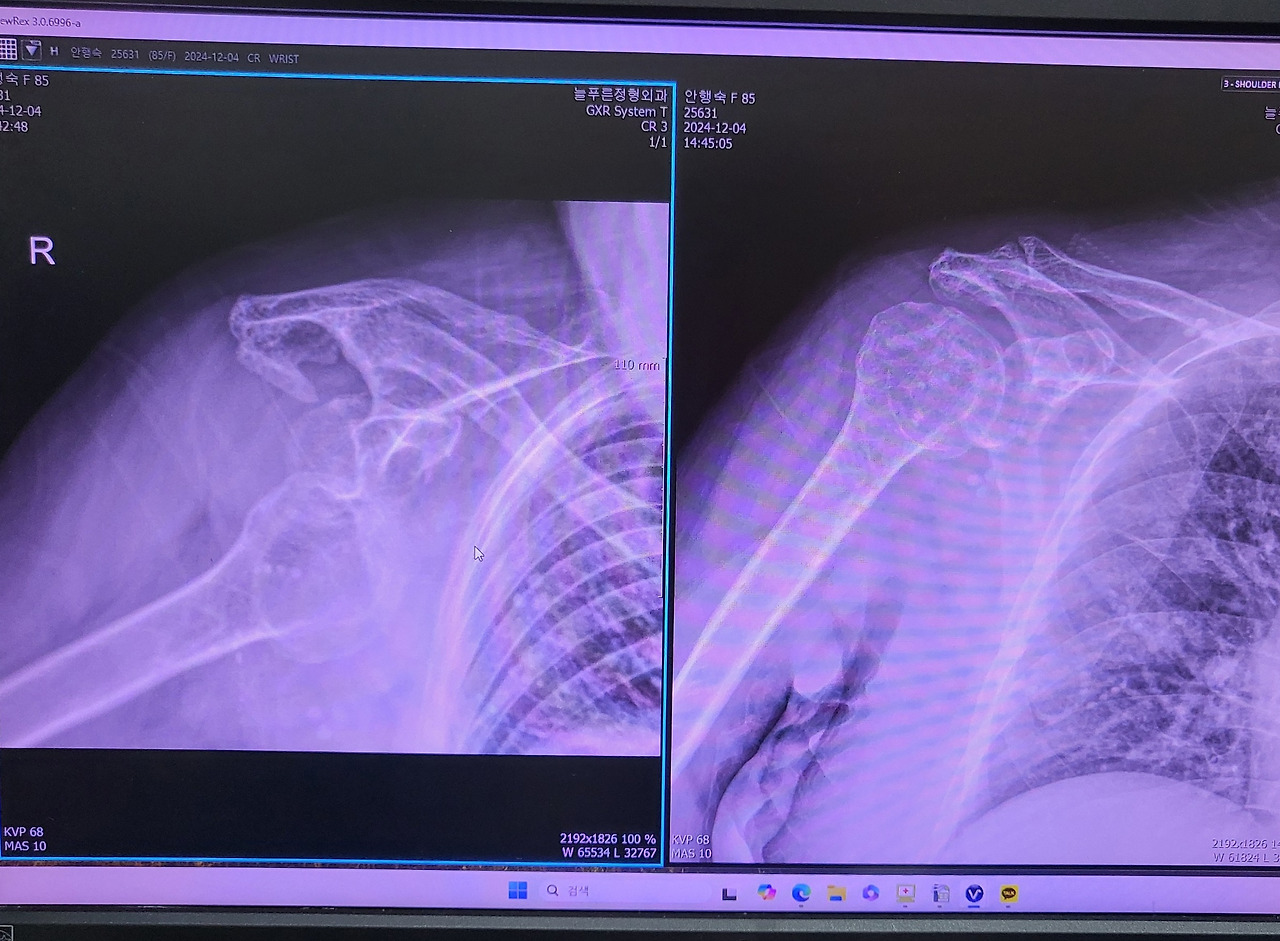

다행히 정신도 맑으시고 한쪽 팔만 아파하시고 우려했던 거보다는 괜찮아 보여 하룻밤 재우고 오늘 정형외과에 다녀왔는데 어깨 탈골이 되셨다네요. 의사 선생님이 생각보다 쉽게 끼워주셨는데 다시 탈골될 수 있대요ㅠㅠ. 앞으로 조심조심 모셔야겠어요.

탈골상태(좌)와 복원후(우)